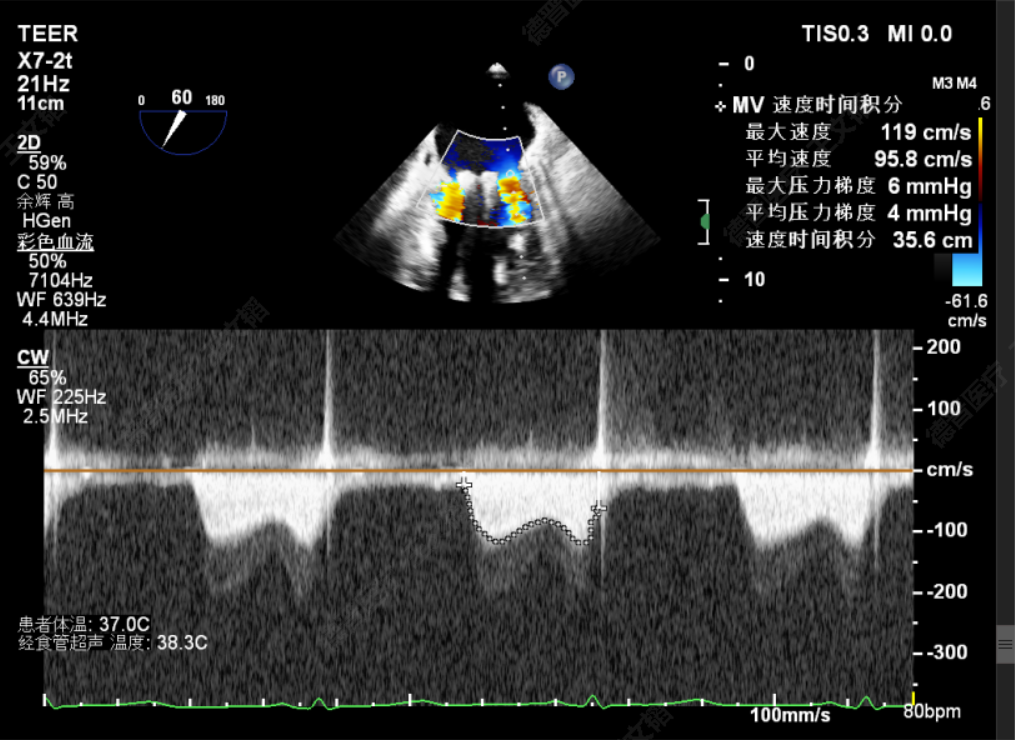

由于该患者情况特殊,潘宏伟教授、何晋教授团队通过讨论决定,先于脱垂正上方置入一枚长宽(XW0612)夹,再根据残余脱垂的情况决定是否置入第二枚夹子。术中团队利用DragonFly™刻度化旋钮及三段式可调节管身的设计,灵活调整二尖瓣夹系统,配合超声老师傅庆华教授的专业引导,成功将二尖瓣安全的打弯至二尖瓣瓣上。最后于2偏1区及2偏3区分别置入了两枚长宽(XW0612)夹。夹闭后反流由术前重度降低为Trace,跨瓣压差4mmHg,左房压由术前61mmHg降至术后27mmHg,肺静脉逆流几乎消失,效果立竿见影。

TMPG:4mmHg

术前肺静脉逆流

术后肺静脉逆流